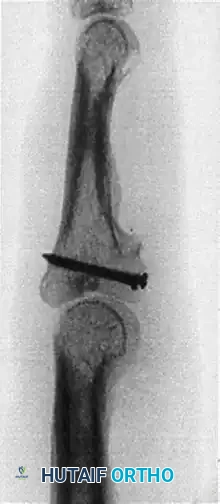

- Definitive Fixation: Fix the graft rigidly in place using two or three 1.0-mm to 1.5-mm screws directed from volar to dorsal. The screws should be placed in lag fashion to compress the graft into the host bone bed. A third screw can be placed in the hole left by the provisional K-wire if the graft size permits.

Volar view of the PIP joint demonstrating the hemi-hamate graft secured with three interfragmentary screws.

Detail of the 1.0 mm or 1.3 mm screws placed through the hamate graft.

Clinical intraoperative photograph showing the hemi-hamate graft held securely in place with interfragmentary screws.

Once the graft is secured, reduce the PIP joint and assess the reduction and hardware placement using intraoperative fluoroscopy.

It is critical to understand that the articular cartilage of the hamate is significantly thicker than the native cartilage of the proximal phalangeal base. Consequently, when the cartilaginous surfaces are perfectly flush and anatomically reduced visually, the subchondral bone lines on the radiograph will not align. This creates an apparent radiographic "step-off." This false step-off should not be worrisome as long as the visual reduction of the articular cartilage was confirmed to be satisfactory prior to joint closure.

Postoperative AP radiograph demonstrating graft incorporation and screw trajectory.

Postoperative lateral radiograph. Note the false articular step-off created by the thicker articular cartilage at the distal hamate compared with the base of the middle phalanx.